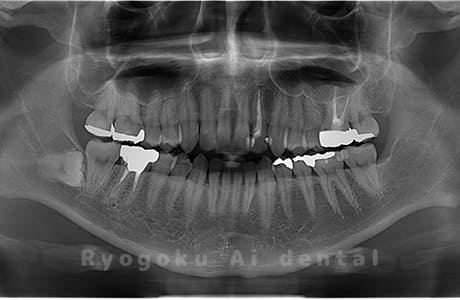

水平埋伏の親知らず

歯茎の中で完全に横に生えてしまうタイプです。

この親知らずを水平埋伏智歯と言います。このタイプはほとんどが下顎のケースです。真横に生えているので抜歯の際は難易度が高く2~3つに砕いて分けて抜歯をします。